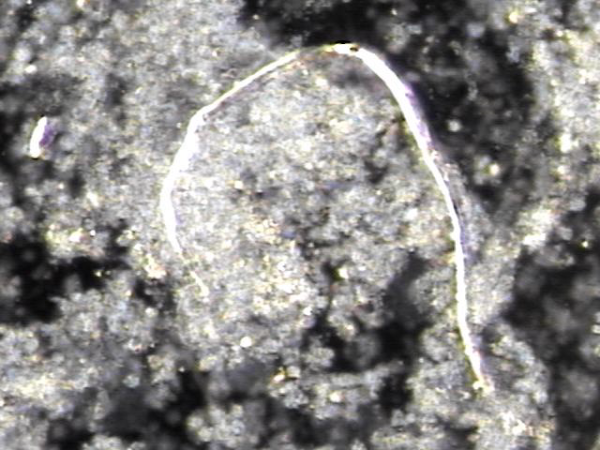

주 1회 전립선의 표적 치료중이라도 하루 약 300만 마리의 정자가 고환에서 생산되어 사정관이 막혀 정자의 순환 장애로 정낭에 모여 혈정액 혹은 정낭 결석과 하복부 통증 그리고 만성 골반통 증후군등의

원인의 치료된 현미경학적 자료입니다.

Even though the testes naturally produce about 3 million sperm every day, blockages in the ejaculatory ducts can sometimes prevent sperm from flowing properly. This can cause semen to build up in the seminal vesicles, leading to blood in the semen, stones, lower abdominal pain, or chronic pelvic pain. Thanks to the targeted treatments, these blockages are being cleared, and this microscopic image shows the tissue after successful treatment.

주 1 치료중 막혀 있던 사정관내 탈락된 상피 세포와 프로스타그란딘에 의한 염증 세포 덩어리가 치료된 현미경학적 자료 입니다.

This microscopic image shows tissue and inflammatory cell clusters that were blocking the ejaculatory duct. These materials, including shed epithelial cells and inflammation caused by prostaglandins, were cleared after twice-weekly targeted treatments.